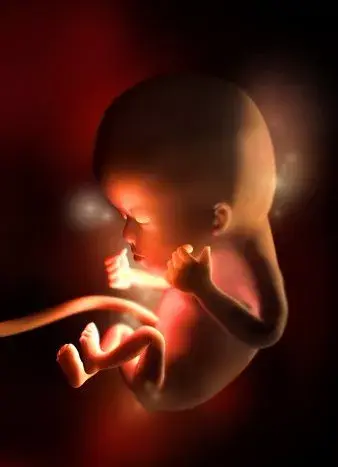

孕早期胎兒發育的過程及B超所見妊娠是一個復雜的過程,卵子受精后,進入宮腔,胚胎及附屬物迅速生長發育直至成熟的過程中,每個孕周都會有不同的變化。

4周:

胎兒只有0.2厘米。受精卵剛完成著床,羊膜腔才形成,體積很小。超聲還看不清妊娠跡象。

5周:

胎兒長到0.4厘米,進入了胚胎期,羊膜腔擴大,原始心血管出現,可有搏動。B超可看見小胎囊,胎囊約占宮腔不到1/4,或可見胎芽。它蘋果籽一樣大小,外觀像個“小海馬”。

6周:

胎兒長到0.85厘米,胎兒頭部、腦泡、額面器官、呼吸、消化、神經等器官分化,B超胎囊清晰可見,并見胎芽及胎心跳。

7周:

胎兒長到1.33厘米,胚胎已具有人雛形,體節已全部分化,四肢分出,各系統進一步發育。B超清楚看到胎芽及胎心跳,胎囊約占宮腔的l/3。此時還聽不到胎心音,但胚胎的心臟已經劃分成左心房和右心室,每分鐘大約跳150下。

8周:

胎兒長到1.66厘米,胎形已定,可分出胎頭、體及四肢,胎頭大于軀干。B超可見胎囊約占官腔1/2,胎兒形態及胎動清楚可見,并可看見卵黃囊。器官已有明顯的特征,手指和腳趾間有少量的蹼狀物。胚胎的各種復雜的器官都開始成長,牙和腭開始發育,耳朵在繼續成形,胎兒的皮膚很薄,血管清晰可見。胚胎開始有運動。

9周:

胎兒長到2.15厘米,胎兒頭大于胎體,各部表現更清晰,頭顱開始鈣化、胎盤開始發育。B超可見胎囊幾乎占滿宮腔,胎兒輪廓更清晰,胎盤開始出現。胎兒所有的器官、肌肉、神經都開始工作,并且發育迅速。手部從手腕開始變得稍微有些彎曲,雙腳開始擺脫蹼狀的外表,眼簾開始覆蓋住眼睛。

10周:

胎兒長到2.83厘米,胎兒各器官均已形成,胎盤雛形形成。B超可見胎囊開始消失,月芽形胎盤可見,胎兒活躍在羊水中 。形狀及大小像一個扁豆莢。胎兒的眼皮開始粘合在一起,直到27周以后才能完全睜開。手腳發育完成,手指和腳趾清晰可見,手臂更長而且肘部變得更加彎曲。胎兒的耳朵發育已經完成。

11周:

胎兒長到3.62厘米,胎兒各器官進一步發育,胎盤發育。B超可見胎囊完全消失,胎盤清晰可見。胎兒開始能做吸吮、吞咽和踢腿動作,胎兒的手指甲和絨毛狀的頭發等細微之處已經開始發育,維持胎兒生命的器官如肝臟、腎、腸、大腦以及呼吸器官也已開始工作。

12周:

胎兒長到4.58厘米,外生殖器初步發育,如有畸形可以表現,頭顱鈣化更趨完善。顱骨光環清楚,可測雙頂徑,明顯的畸形可以診斷,此后各臟器趨向完善。手指和腳趾已經完全分開,部分骨骼開始變得堅硬,并出現關節雛形。